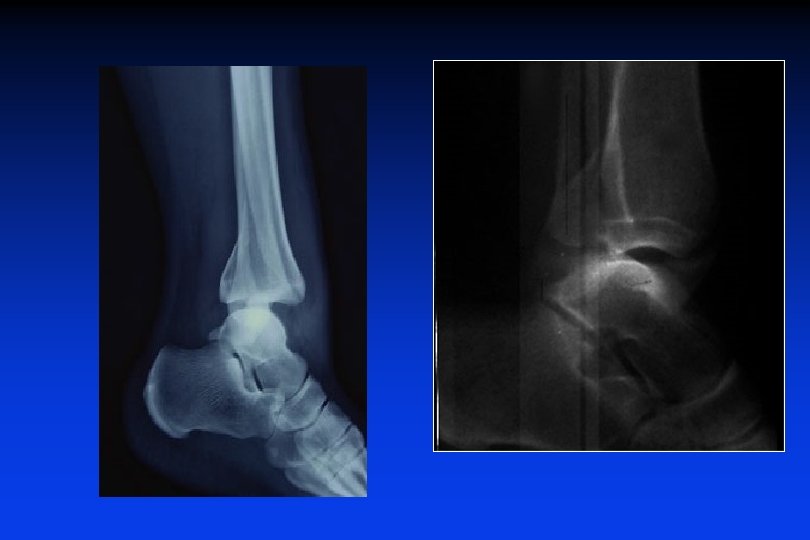

Commentez cette radiographie